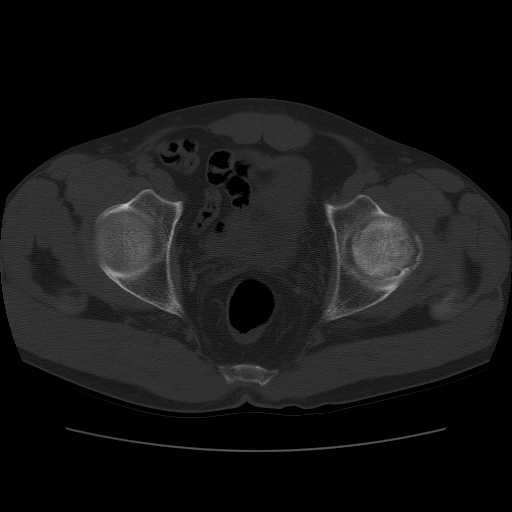

标题: CT11650:左髋病变,请会诊. [打印本页]

标题: CT11650:左髋病变,请会诊.

左髋疼痛不适近半年,局部无红肿热.无明确外伤病史.黄酒每天二餐.

考虑左侧股骨头缺血性坏死.(常期饮酒引起代谢障碍?)

左侧股骨头缺血性坏死;很典型。

“局部无红肿热.无明确外伤病史.黄酒每天二餐”。考虑左侧股骨头缺血性坏死。